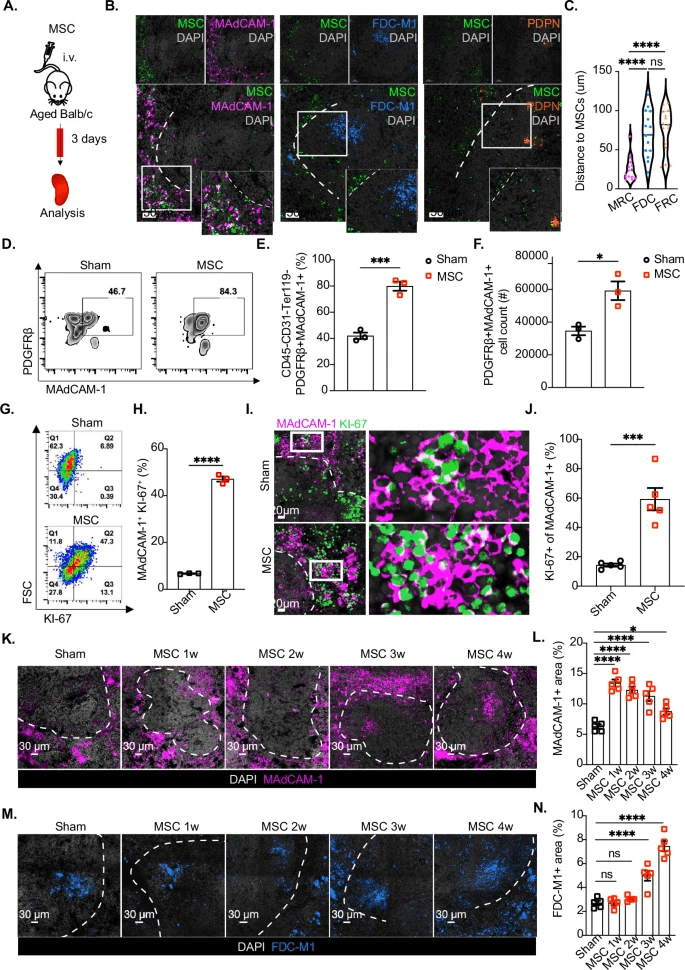

本研究首次在临床前及早期临床试验中系统验证了诱导多能干细胞(iPSC)来源的自然杀伤细胞经腹腔灌注后,在卵巢癌、腹膜癌等腹腔内播散性肿瘤模型中的靶向性、持久性与抗肿瘤活性。研究团队通过基因工程增强scNK细胞的NKG2D和CD16表达,显著提升其对肿瘤细胞表面应激配体的识别能力,并在无IL-2支持下实现体内持续存活超过21天。